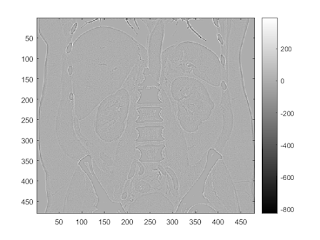

laplacian of gaussian

b = fspecial('log'); I2 = conv2(I,b,'same'); imagesc(I2); colorbar